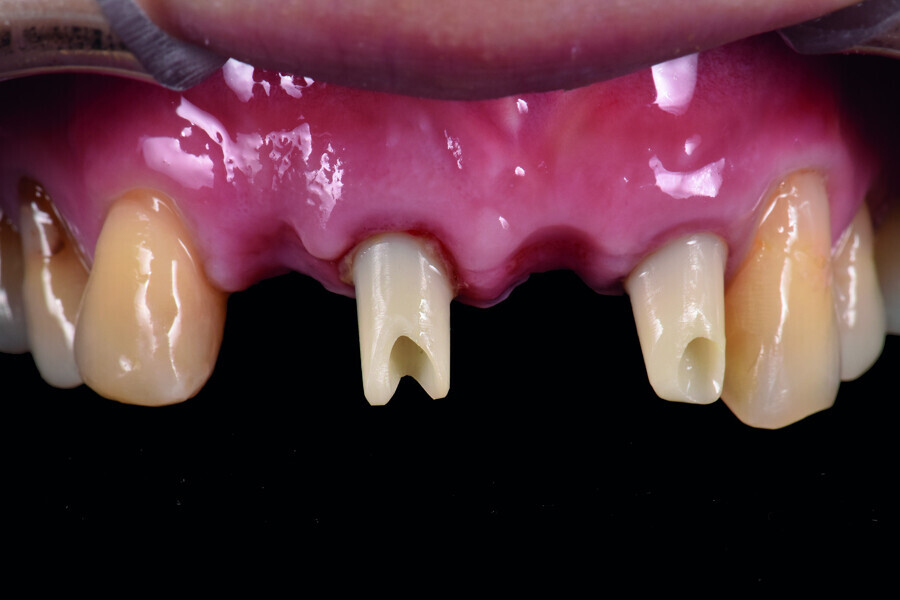

Fig. 2: Pre-op occlusal view of the anterior teeth.